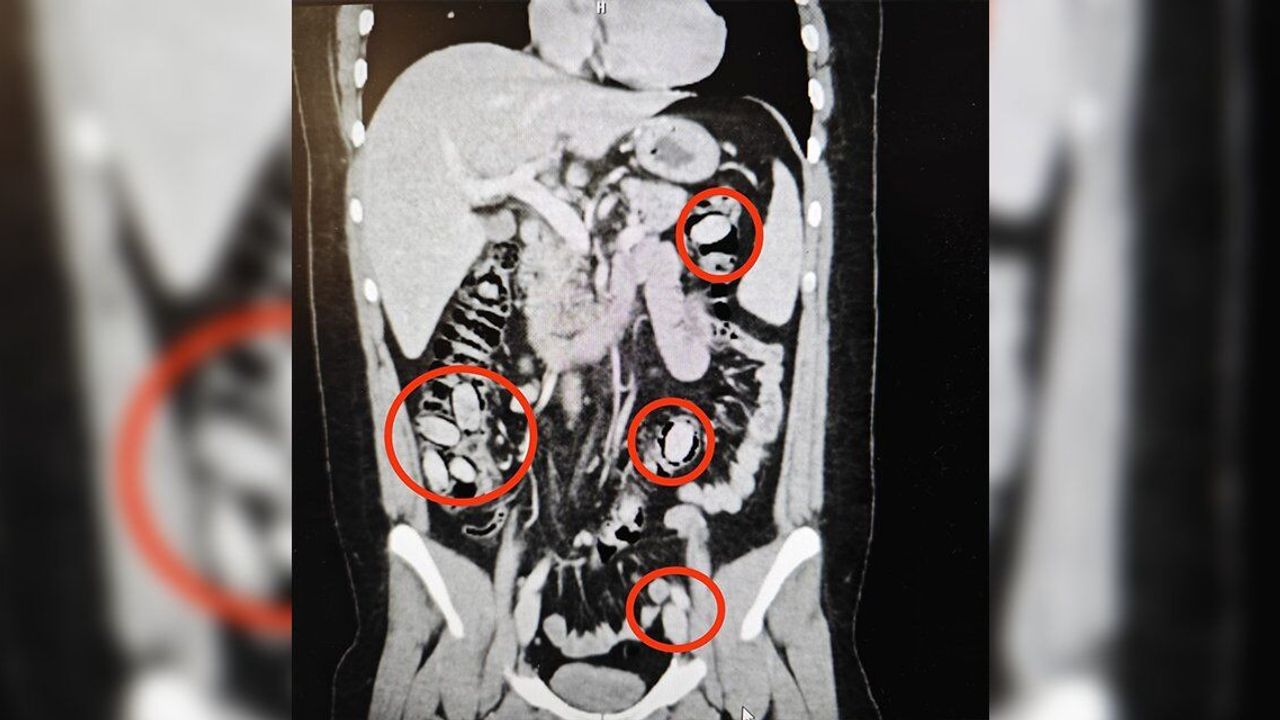

Yurtdışından Eskişehir'e gelen S.A. (25) isimli yabancı uyruklu şahsın kent girişindeki çevirme noktasında durumundan şüphelenilmesi üzerine hastanede yapılan detaylı tetkikler neticesinde yutmak suretiyle midesinde 44 kapsül metamfetamin maddesi taşıdığı anlaşıldı. Cerrahi müdahaleyle sözkonusu maddeler şahsın bedeninden çıkarıldı. Tedavisi akabinde şahıs tutuklandı. Yapılan titiz operasyon ile uyuşturucu maddelerin Eskişehir'de piyasaya sürülmeden ele geçirilmesi sağlandı.